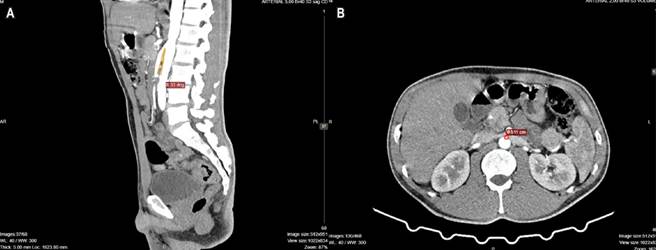

In previous hospitalizations, the patient had received symptomatic pain management with partial improvement. Due to persistent abdominal pain, the Internal Medicine team ordered a contrast-enhanced computed tomography (CT) scan, which revealed dilation between the second and third portions of the duodenum. A transition zone was identified at the level of the aortomesenteric clamp, with a reduced angle of less than 8° between the superior mesenteric artery and the aorta, and an aortomesenteric space measuring only 5 mm. There was no evidence of left renal vein dilation or stenosis. These findings are consistent with a diagnosis of aortomesenteric duodenal compression syndrome (Figure 1).

Figure 1 Double-Contrast Total Abdominal Tomography. A. Sagittal section, arterial phase. The aortomesenteric clamp is visualized at an angle of 8º. B. Cross section, arterial phase. The aortomesenteric distance of 5 mm is visualized. Images property of the authors.